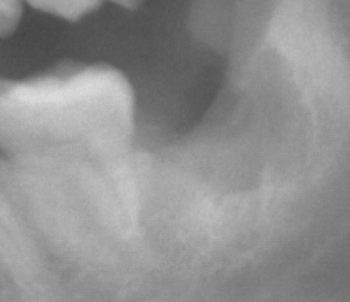

取り出すと根の先がこの状態でして、、、ブラブラに動いていたのですが、先がひっかかって取れなかったのです!

きれいに取れてよかったです!

レントゲンで見て最悪は削って時間がかかりますよと説明していたのですが、自分の想像以上に時間がかかってしまい申し訳ありませんでした!汗! |